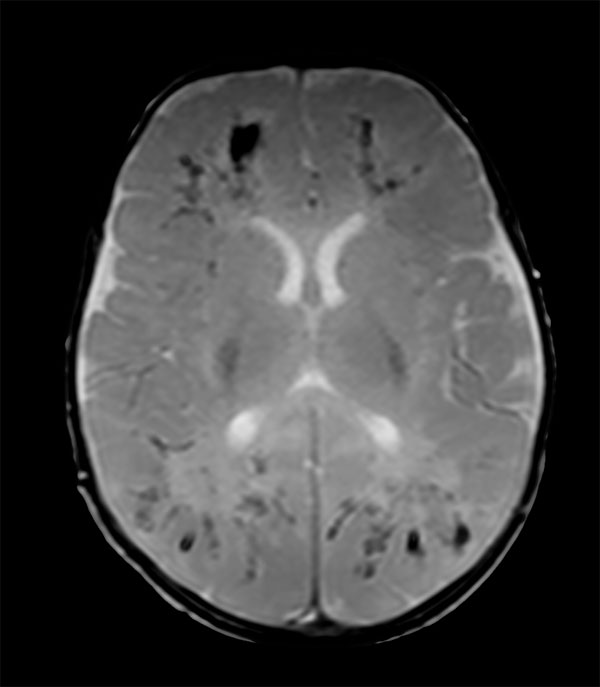

Axial SWIp

Axial 3D SWIp